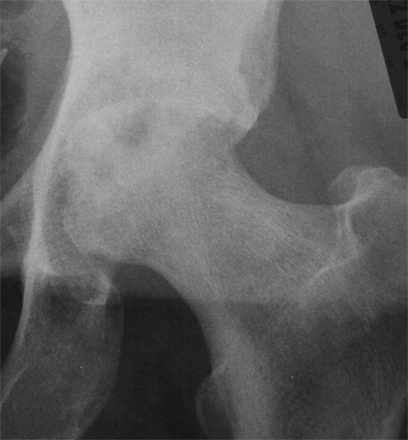

Patients usually present with a very rapid onset of severe pain and signs of toxicity. In patients who are very immuno-compromised there may not be the usual signs of systemic reaction to infection. In the early stages x-rays may mimic arthritis or AVN.

MRI is very sensitive but may still struggle to differentiate between advanced sepsis and AVN.